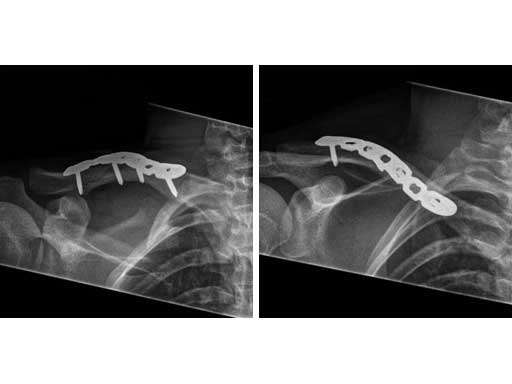

Fig 3ab Immediate postoperative x-rays.

Fig 4ab X-rays 9 months postoperatively.